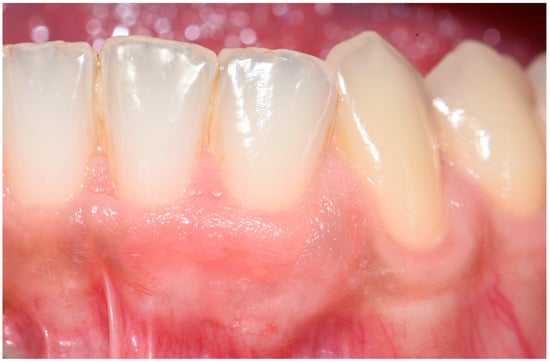

2. Case Report